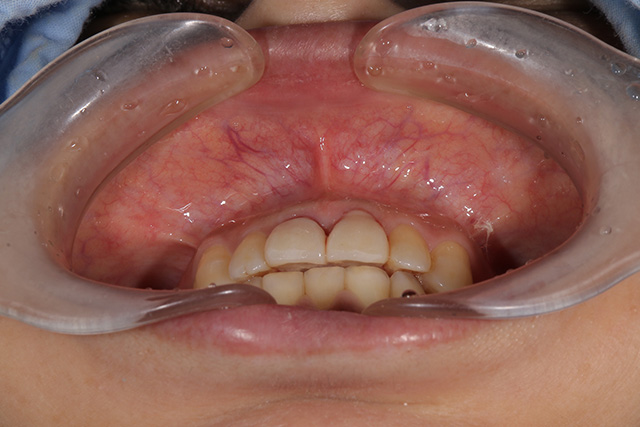

審美症例